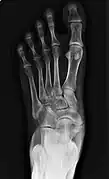

![]() X-ray of the foot showing an accessory navicular bone | |

An accessory navicular bone is an accessory bone of the foot that occasionally develops abnormally in front of the ankle towards the inside of the foot. This bone may be present in approximately 2-14% of the general population and is usually asymptomatic.[1][2][3] When it is symptomatic, surgery may be necessary.